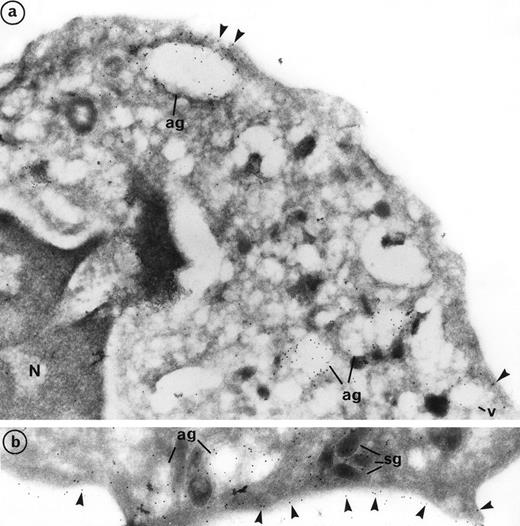

Labeling of PR3 with the mouse monoclonal CLB 12.8 showed immunogold grains on the plasma membrane as well as within intracellular granular compartments. PR3 labeling was also observed at the periphery of large extracted granules, the azurophil granules (ag), and empty vesicles (v) (Fig 3a). Plasma membrane labeling of PR3 was homogeneous on the cell surface and was not restricted to certain areas (Fig 3b). However, the intensity of this labeling varies from one neutrophil to another, thus confirming the heterogeneity of PR3 membrane labeling measured by flow cytometry using the same antibody CLB12.8. In the donor that we present in Fig 3, 80% of neutrophils were positive for PR3 membrane labeling and 20% were negative. However, all neutrophils showed azurophil granule labeling. Figure 3a shows a neutrophil with weak PR3 membrane labeling, although azurophil granule labeling was present. Figure 3b shows a neutrophil with intense PR3 membrane labeling.

Subcellular localization of PR3 by electron microscopy on neutrophils thin frozen sections labeled with anti-PR3. Electron micrograph of resting neutrophils from the same individual stained for localization of PR3 with the MoAb anti-PR3 CLB 12.8 followed by incubation with 10-nm gold particles-conjugated goat antimouse (GAM 10). (a) Gold-labeled antibody is present at the periphery of large extracted granules identified as the azurophil granules (ag) as well as in the membrane of intracellular empty vesicles (v). Plasma membrane labeling is shown by arrow heads (original magnification × 35,200). (b) The immunogold label (arrowheads) indicates the presence of PR3 on the plasma membrane in a random distribution head (original magnification × 42,550).

Double labeling of PR3 with MPO confirmed that PR3 is located with MPO in the azurophil granules (ag) that represent the major intracellular store of PR3 (Fig 4a). Azurophil granules appeared as large empty extracted granules with strong intragranular MPO labeling. Previous electron microscopy studies have pointed out the particular trend of azurophil granules to be extracted, which made them look lighter than the other granules.33 Azurophil granules were abundant and in clusters within neutrophil cytoplasm. PR3 labeling was mainly restricted to the periphery of granules. In contrast to MPO, PR3 labeling also appears in the membrane of small empty vesicles (v). PR3 labeling can be detected in the limiting membrane of some dense and small granules, with an elongated form characteristic of specific granules (sg) (Figs 3b and 4a, b, and d). This labeling was weak but appeared to be significantly higher than background labeling on mitochondria taken as control. Double-labeling PR3 with lactoferrin confirmed that PR3 is present in the membrane of lactoferrin-containing granules (Fig 4b).